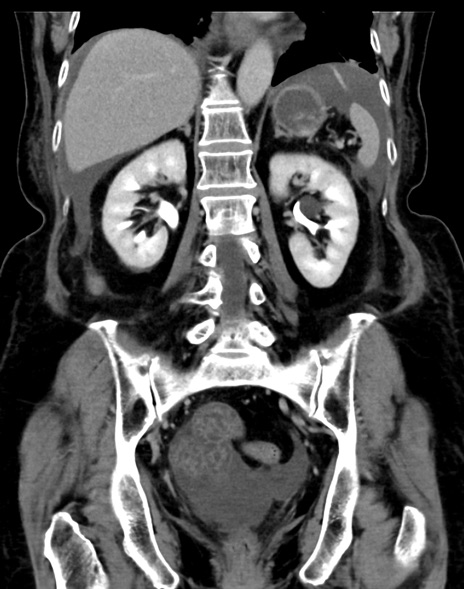

(横断像)1日半後